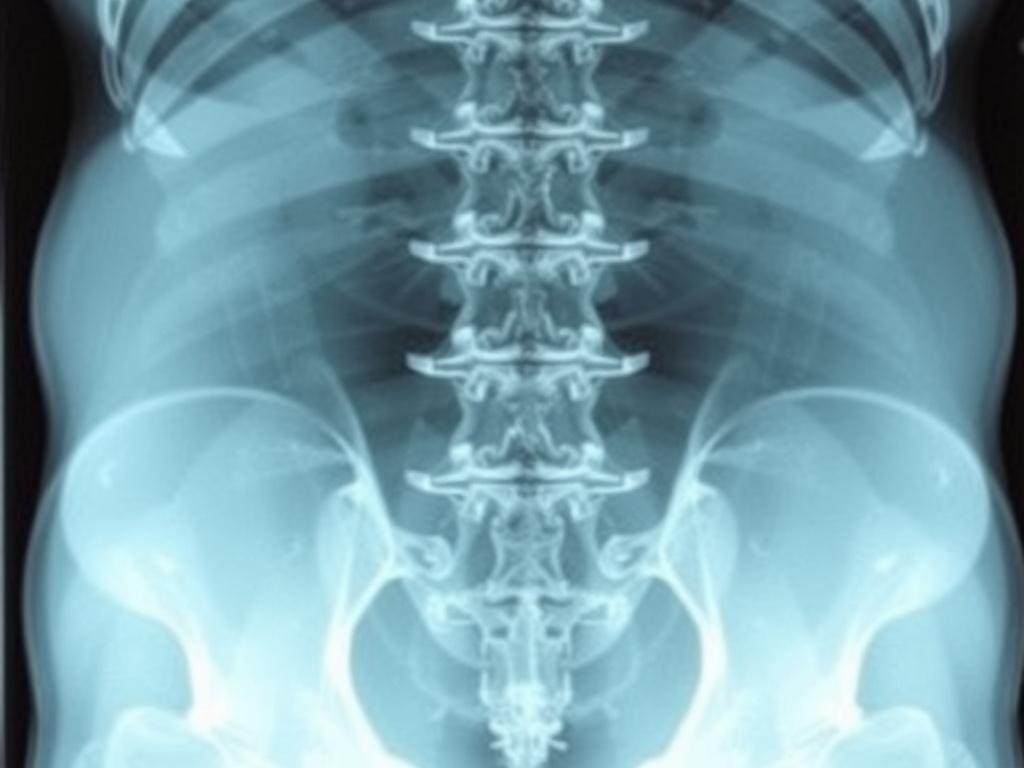

Рентген — это снимок костей с помощью Х-лучей. Луч проходит через тело, кости задерживают его сильнее, чем мягкие ткани. Поэтому позвонки на изображении видны ясно, как белый каркас. Снимок делают в двух проекциях: спереди и сбоку. Иногда добавляют функциональные пробы. Человек делает наклон или разгибание. Так врач видит, как двигаются позвонки.

Рентген хорошо видит кости. Поэтому он показывает:

• высоту тел позвонков и межпозвонковых промежутков;

• переломы, трещины, клиновидную деформацию;

• остеофиты и признаки спондилеза;

• сколиоз и степень искривления;

• смещение позвонков друг относительно друга.

Диск сам по себе на рентгене не виден. Также не видно нервные корешки и мышцы. Если важно оценить грыжу, отек, канал — лучше МРТ. Если важно увидеть костные детали до миллиметра — поможет КТ.